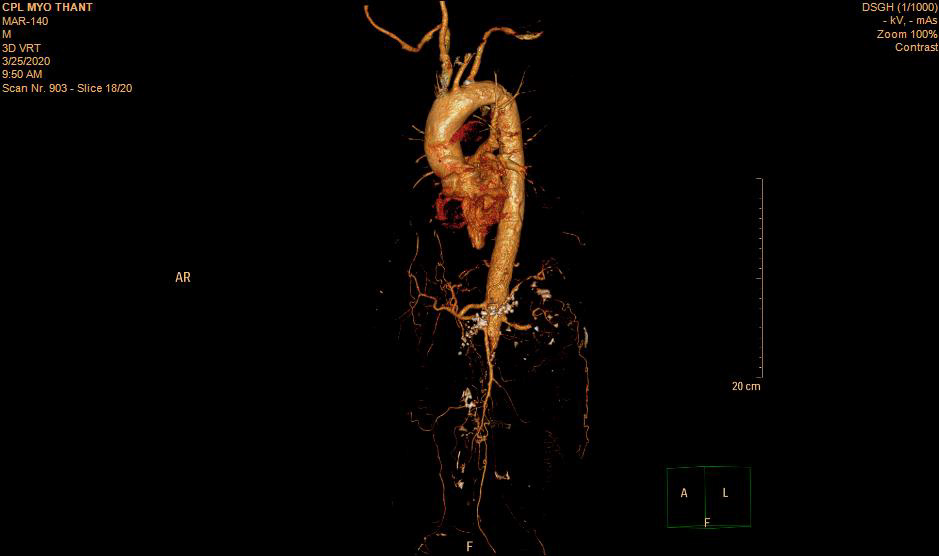

As his left femoral artery pulsation became weak and thus, CT Aortogram was done (4 weeks after symptom onset of right femoral artery occlusion). It revealed extensive thrombosis with complete obstruction of abdominal aorta starting below the level of celiac trunk- both renal arteries and both iliac arteries. The calcifications of the arterial wall at aortic arch, thoracic and abdominal aorta and both iliac vessels were seen too. (Figures 5-11) Thus, he had severe atherosclerosis due to hypertension and heavy smoking. Occlusion of both renal arteries explained his high blood pressure. The cholesterol and uric acid level were normal. He was treated with atorvastatin, aspirin, clopidogrel, antihypertensives, wound care, physiotherapy, intensive nursing care nutritional support and antibiotics.